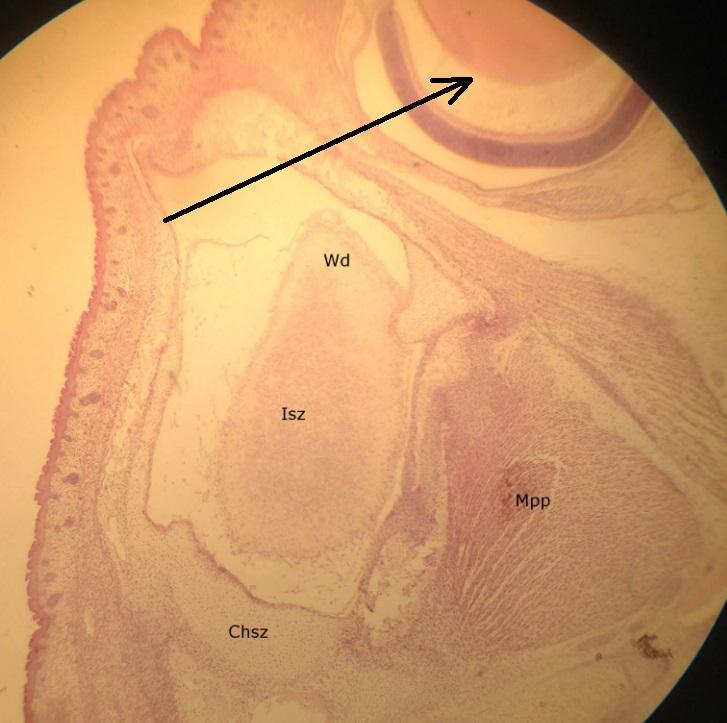

Pytanie 355

gruczoły łzowe (preparat rozwojowy z głowy szczura, zawiązek oka)